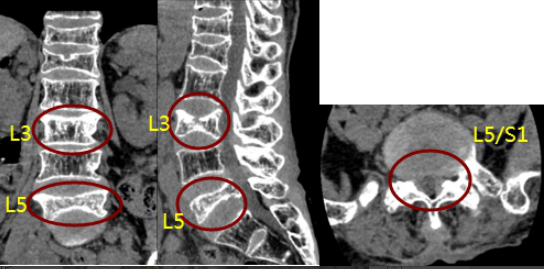

2020年08月27日,州人民医院骨科主任医师吴俊一收治了一位特殊的女性患者:73岁,因“反复腰腿痛20+年,加重20+天”入院。术前诊断:1、腰椎椎管狭窄伴神经损害;2、腰3、腰5椎体病理性骨折;3、胸12、腰1椎体陈旧性压缩骨折;4、重度骨质疏松;5、左侧股骨转子间骨折畸形愈合。

综合考虑患者病情,常规椎弓根螺钉置钉技术,固定失败率较高,难以取得良好的手术目的及效果。向患方交代相关问题后,患者希望手术的愿望强烈。经积极完善术前准备,在州人民医院与四川省人民医院搭建的“传帮带”平台上聘请了四川省人民医院俞阳副主任医师,于2020年9月9日在全麻下为患者进行了“腰3椎体成形术+经后路腰4-骶1椎椎管减压术+腰4/5、L5/S1神经根探查松解术+腰4/5、腰5/骶1椎间盘摘除、椎间植骨融合+骨水泥强化椎弓根钉内固定术”。手术在历时5小时30分钟后顺利结束。术后患者恢复好,局部疼痛明显缓解,术后需长时间防治骨质疏松治疗,目前患者腰腿疼情况已好转,生活质量得到明显的改善。